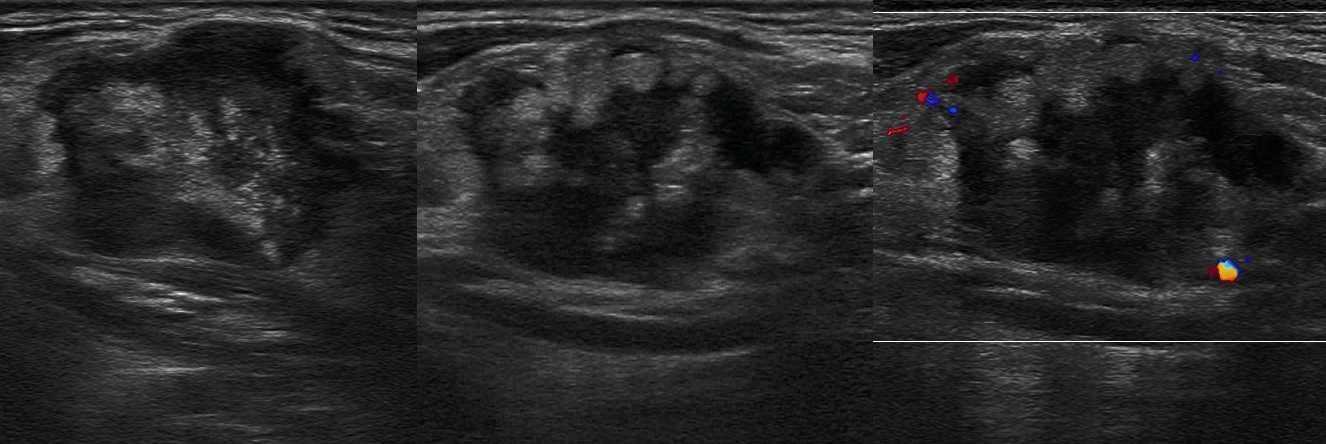

Вступая в борьбу с инфекцией лимфоузлы воспаляются. Воспалённые лимфоузлы стремительно «растут» в начале болезни и быстро «сдуваются» при выздоровлении. На УЗИ лимфоузел увеличен за счет корковой и околокорковой зоны, гипоэхогенный по периферии и гиперэхогенный в центре, форма овальная, контур четкий, кровоток только в воротах или отсутствует. Если воспаление переходит в окружающую клетчатку (периаденит), то может сформироваться абсцесс.

Рисунок. У детей с ОРВИ на УЗИ увеличенные шейные лимфоузлы с сохранной архитектурой — овальной формы, контур четкий и ровный, гипоэхогенные по периферии с гиперэхогенным центром. Заключение: Лимфаденопатия шейных лимфоузлов.

Рисунок. Женщина жалуется на «опухоль» в подмышке и на локте. Неделю назад повздорила с соседской кошкой. На УЗИ подмышечный (сверху) и локтевые (снизу) лимфоузлы увеличены, округлой формы, выраженная гиперплазия корковой и околокорковой зоны, гиперэхогенный центральный рубчик сохранен; кровоток заметно усилен, сосуды расположены правильно — радиально. Заключение: Лимфаденопатия с признаками высокой степени активности. При болезни кошачьей царапины на месте укуса или царапины образуются небольшие гнойнички и одновременно воспаляются близкие лимфоузлы. Один или группа лимфоузлов увеличиваются в размерах до 5-10 см, становятся болезненными, уплотняются. Через 2-4 недели происходит самоизлечение. Иногда образуются абсцессы и свищи.